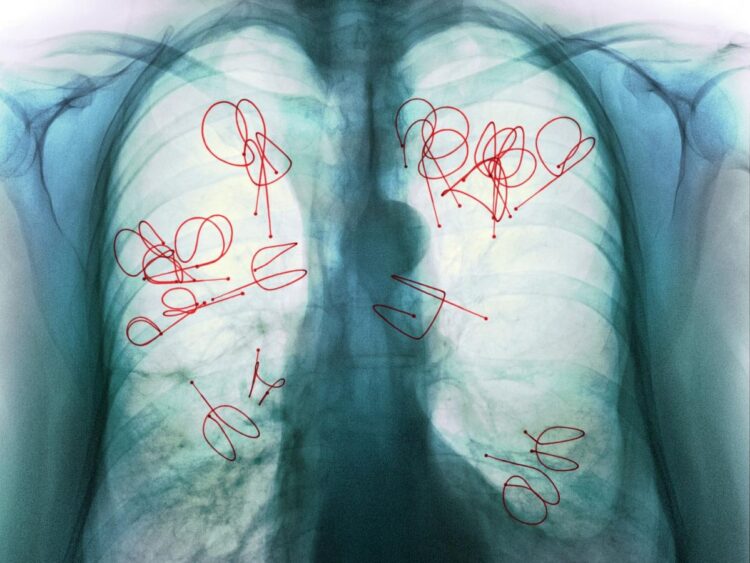

Lancement d’une Campagne de Sensibilisation Nationale contre la tuberculose

Le ministère de la Santé et de la Protection Sociale a initié une importante campagne de lutte contre la tuberculose, intitulée «Respirez la vie… Luttez contre la tuberculose », qui a pris son essor le 1er novembre et qui se déploiera sur une durée de six semaines. Dans un contexte où la réduction de l’incidence de la maladie progresse timidement, ce programme national est une étape cruciale pour sensibiliser et promouvoir le dépistage précoce de la tuberculose, un enjeu de santé publique toujours prégnant au Maroc.

Les données récentes révèlent une persistance alarmante de la pathologie, avec plus de 30 000 cas rapportés en 2022, y compris des formes de tuberculose résistantes aux traitements pharmaceutiques. Malgré une couverture de détection et de guérison satisfaisante, dépassant les 85% et avoisinant les 90% respectivement, la diminution annuelle de l’incidence se situe entre 1 et 2%, un rythme insuffisant pour envisager une éradication d’ici 2030.

Le spectre de la pandémie de COVID-19 a également accentué les défis, exacerbant la situation épidémiologique et les efforts contre cette maladie. Par ailleurs, le repérage insuffisant des cas infantiles et l’émergence de souches résistantes soulignent la nécessité d’une stratégie robuste et concertée. La campagne s’inscrit dans le cadre du plan stratégique national 2021-2023, aligné sur l’initiative de l’OMS et les Objectifs de développement durable, visant une réduction significative de la mortalité due à la tuberculose.

L’urbanisation dense et les conditions précaires des zones périurbaines accentuent la vulnérabilité face à la tuberculose, exacerbée par des facteurs tels que la malnutrition et l’habitat insalubre. Les symptômes de la tuberculose sont souvent trompeurs et peuvent affecter divers organes au-delà des poumons.

Le diagnostic précoce est impératif et l’OMS préconise l’utilisation de tests moléculaires rapides, tels que Xpert MTB/RIF Ultra et Truenat, pour leur précision diagnostique. Le traitement nécessite un engagement à long terme dans la prise d’antibiotiques pour éviter toute résistance médicamenteuse, particulièrement critique dans les cas de tuberculose pharmacorésistante.

Cet élan de sensibilisation marque un pas supplémentaire vers la compréhension et la gestion effective de la tuberculose au Maroc, reconnaissant la nécessité d’une approche multisectorielle pour faire face à cette menace pour la santé publique.